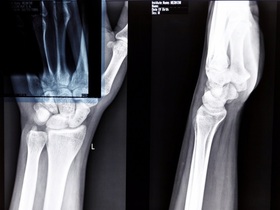

Инструментальная диагностика подагры:

- УЗИ суставов и почек;

- рентген "целевых" суставов;

- двойная энергетическая компьютерная томография суставов;

- МРТ.